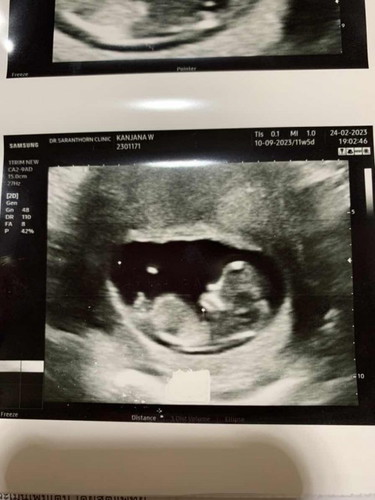

บ้านนี้ ซาวด์ 11w5d เจอจู๋น้อยๆ เเม่ๆว่าใช่ไหมค่ะ บ้านนี้ตื่นเต้นมาก ป้าหมอให้% ผู้ชาย90% เลยค่า 🥹🥰 #ขอบคณุล่วงหน้าสำหรับคำตอบนะค่ะ

ใช่ไหมเเบบนี้55555ซาวตอน11+5